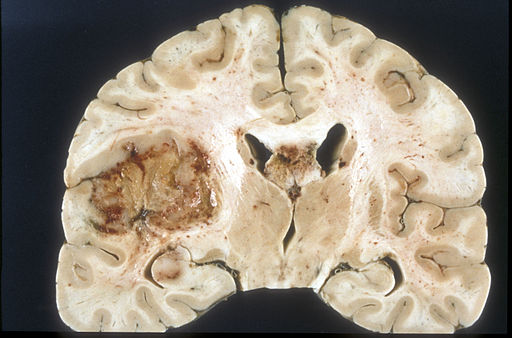

Nádory mozku nebo také intrakraniální nádory jsou takové nádory, které postihují mozek a mozkové obaly (mozkové pleny). Může se jednat jak o nádory primární, tedy o nádory vzniklé přímo z příslušných tkání, tak i o nádory sekundární, tedy metastázy jiných nádorů ať už z mozku nebo z těla. Vzhledem k tomu, že tyto nádory rostou v uzavřeném prostoru lebky, liší se od jiných nádorů svým chováním a mnohdy i symptomatologií. Wikipedie